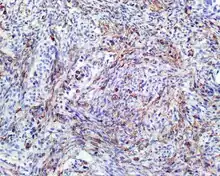

S100 protein reaction in a biphenotypic sinonasal sarcoma

• S100 protein (a tumor marker protein) is focal, patchy to diffuse in all tumors.

• Smooth-muscle actin or muscle-specific actin is seen in nearly all tumors, but a strong and diffuse reaction with SMA is seen in only about 50% of cases.